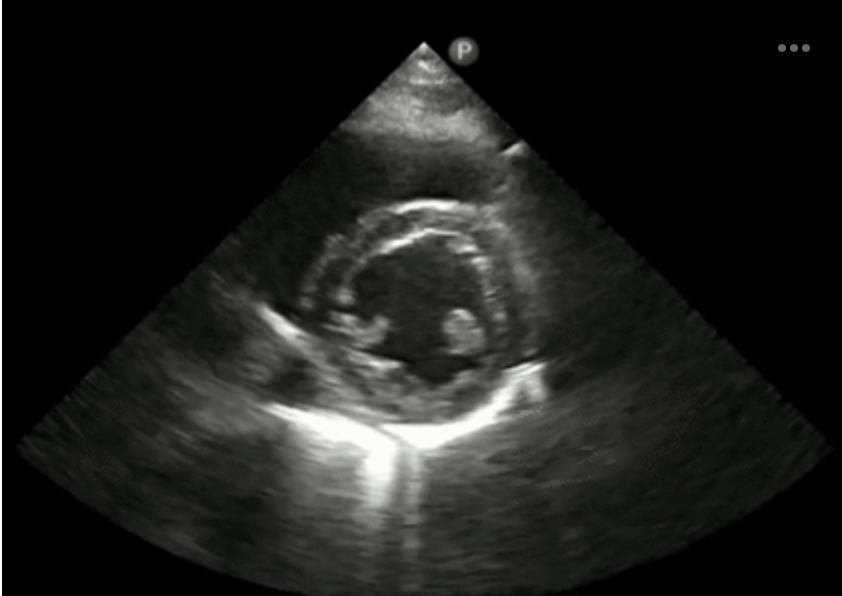

Identify the level of the LV at the blue box, yellow box and red box.

basal-blue Mid-yellow Apical-red